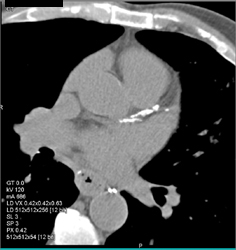

Diagnosis

Diseased LAD